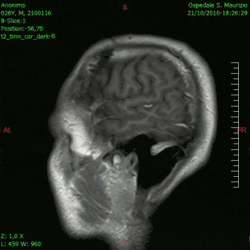

En las imágenes de TC y RM se muestra como una lesión heterogénea, de contorno irregular, que capta contraste en anillo y con un área central necrótica.

Diagnóstico por imagen y glioblastoma

La TC muestra una lesión de morfología irregular, predominantemente hipodensa y fuertemente dishomogénea, debido a la presencia de grandes áreas necróticas de más clara hipodensidad y de áreas sólidas hiperdensas. Estas últimas son la expresión de un rápido crecimiento y por lo tanto de una elevada malignidad. Son frecuentes las zonas hemorrágicas, que van desde pequeños focos a grandes áreas hemáticas que pueden cubrir toda la lesión. Es característica la morfología en "mariposa" si el tumor se asienta en ambos hemisferios a través del cuerpo calloso.

Tras la aplicación de contraste aparecen gruesos anillos alrededor de las áreas necróticas. En la RM, la parte sólida aparece hipointensa en T1 e hiperintensa en T2 con zonas de señal más elevada en las partes de mayor celularidad. Las áreas necróticas, hiperintensas en T2, pueden presentarse hipo-, iso- o hiperintensas en T1 en función del contenido proteico o de productos de la degradación de la hemoglobina. El realce tras el contraste suele ser intenso e irregular en la periferia del tumor e identifica sobre todo la componente celular "proliferativa" de la neoplasia. Son comunes las áreas puntiformes y serpiginosas de ausencia de señal de flujo, asociadas a la presencia de una neovascularización rica. Estos vasos de neoformación patológica carecen de barrera hematoencefálica, lo que explica tanto la abundante impregnación como el edema vasogénico perilesional (véase la sección anterior), debido al paso de líquido al medio extracelular.[72][73]

Animación en el plano sagital de un caso de resección total gruesa de un glioblastoma -